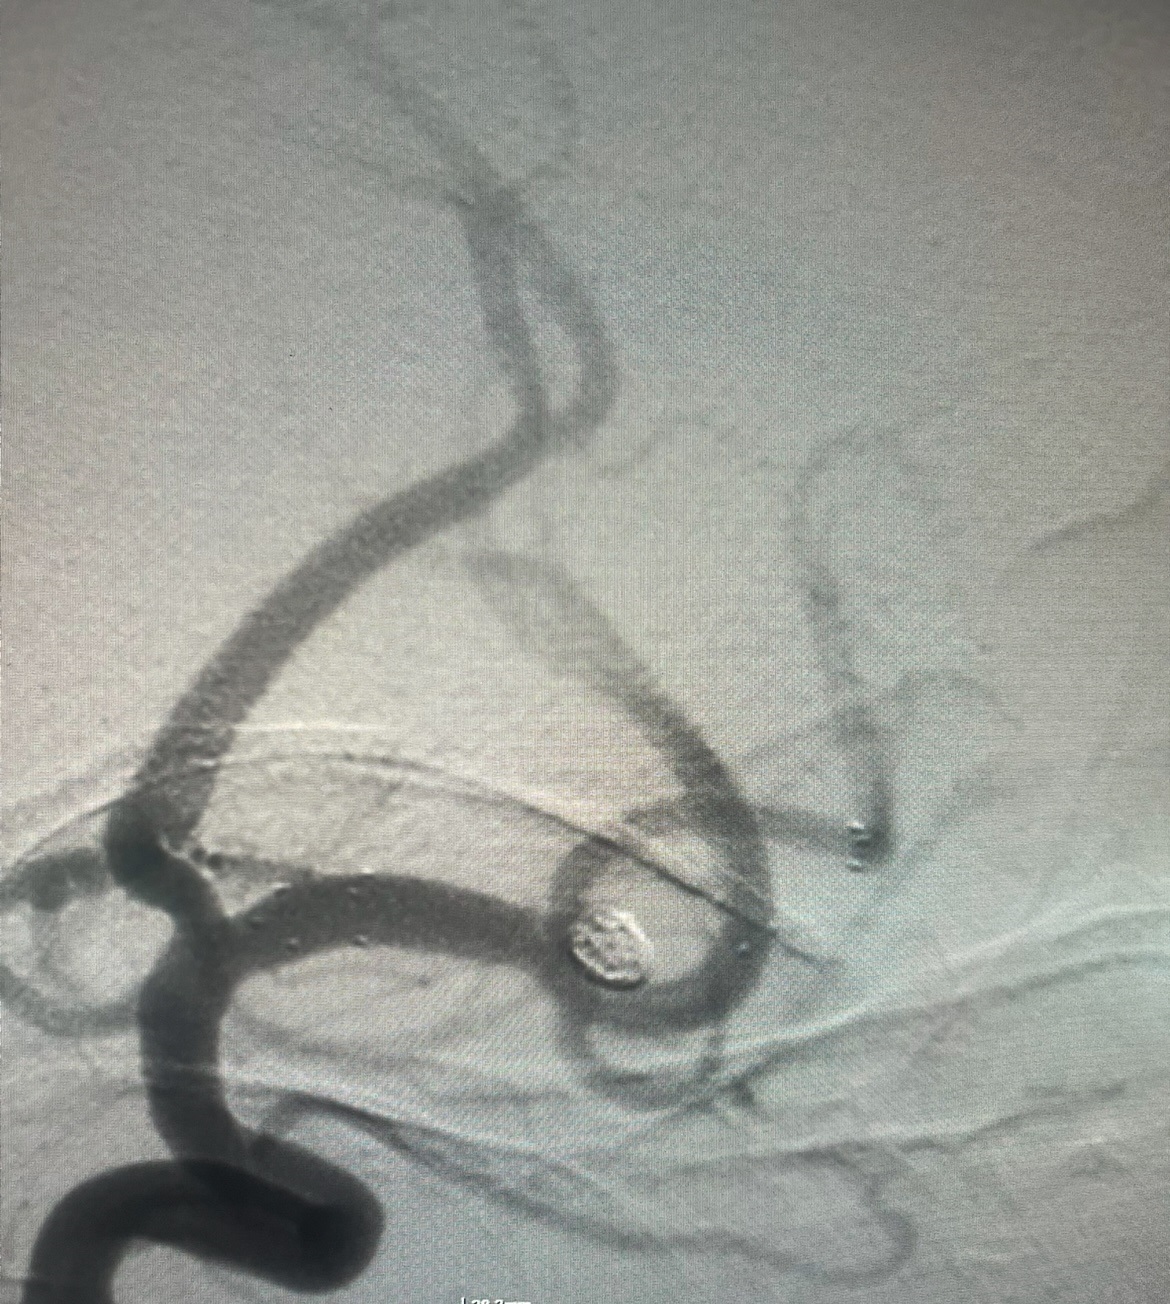

Εμβολισμός ανευρύσματος της αριστερής μέσης εγκεφαλικής αρτηρίας

Και η ενδαγγειακή προσεγγίση. Κατά την προσέγγιση αυτή, πλοηγούμε τα υλικά μέσα από τις αρτηρίες και τοποθετούμε μέσα στο ανεύρυσμα μεταλλικά σπειράματα (coils) μόνα ή σε συνδυασμό με ενδοπρόθεση (stent) ή τοποθετούμε ειδική κατηγορία ενδοπρόθεσης (stent) τροποιητή της ροής στην αρτηρία που φέρει το ανεύρυσμα.